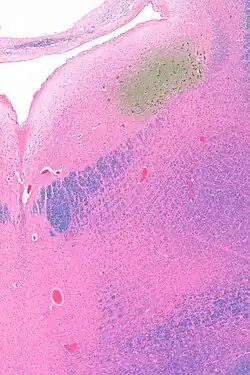

Micrograph showing the locus coeruleus (upper-right of image) in an axial section of the pons. The fourth ventricle (quasi-triangular white area) is in the upper-left of the image. The midline is seen on the left. The large white area in the upper-left corner is where the cerebellum would be. HE-LFB stain.

Micrograph showing the locus coeruleus. HE-LFB stain

The locus coeruleus (LC) is located in the posterior area of the rostral pons in the lateral floor of the fourth ventricle. It is composed of mostly medium-size neurons. Melanin granules inside the neurons contribute to its blue colour. Thus, it is also known as the blue nucleus, or the nucleus pigmentosus pontis (heavily pigmented pontine nucleus).[5] The neuromelanin is formed by the polymerization of norepinephrine and is analogous to the black dopamine-based neuromelanin in the substantia nigra.